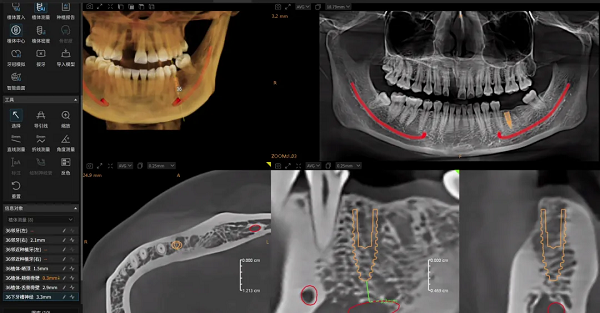

2.智能规划:从经验依赖到人机协同的进化

面对复杂手术规划,Dental X云平台能基于患者影像数据,由AI自动生成包含植入位置、角度和深度的三维规划方案。这不仅大幅缩短了规划时间,其科学性更为医生提供了可靠的参考基准,让医生能将核心精力集中于方案的个性化调整与优化,实现人机协同的决策模式。

当规划方案确认后,AI可一键生成与之精确匹配的手术导板,并支持椅旁3D打印,助力诊所构建“数据采集→诊断分析→方案设计→导板打印”的全流程数字化闭环。这一革新将传统流程平均3天耗时,大幅缩短至约1.5小时,真正实现了种植诊疗的效率和精准革命。